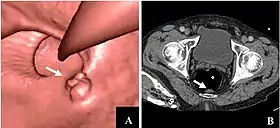

![]() CT colonography of a rectal mass. Left image is a volume rendering and right image is a thin slice. It also shows the rectal tube used for insufflation of gas to distend the colon. | |